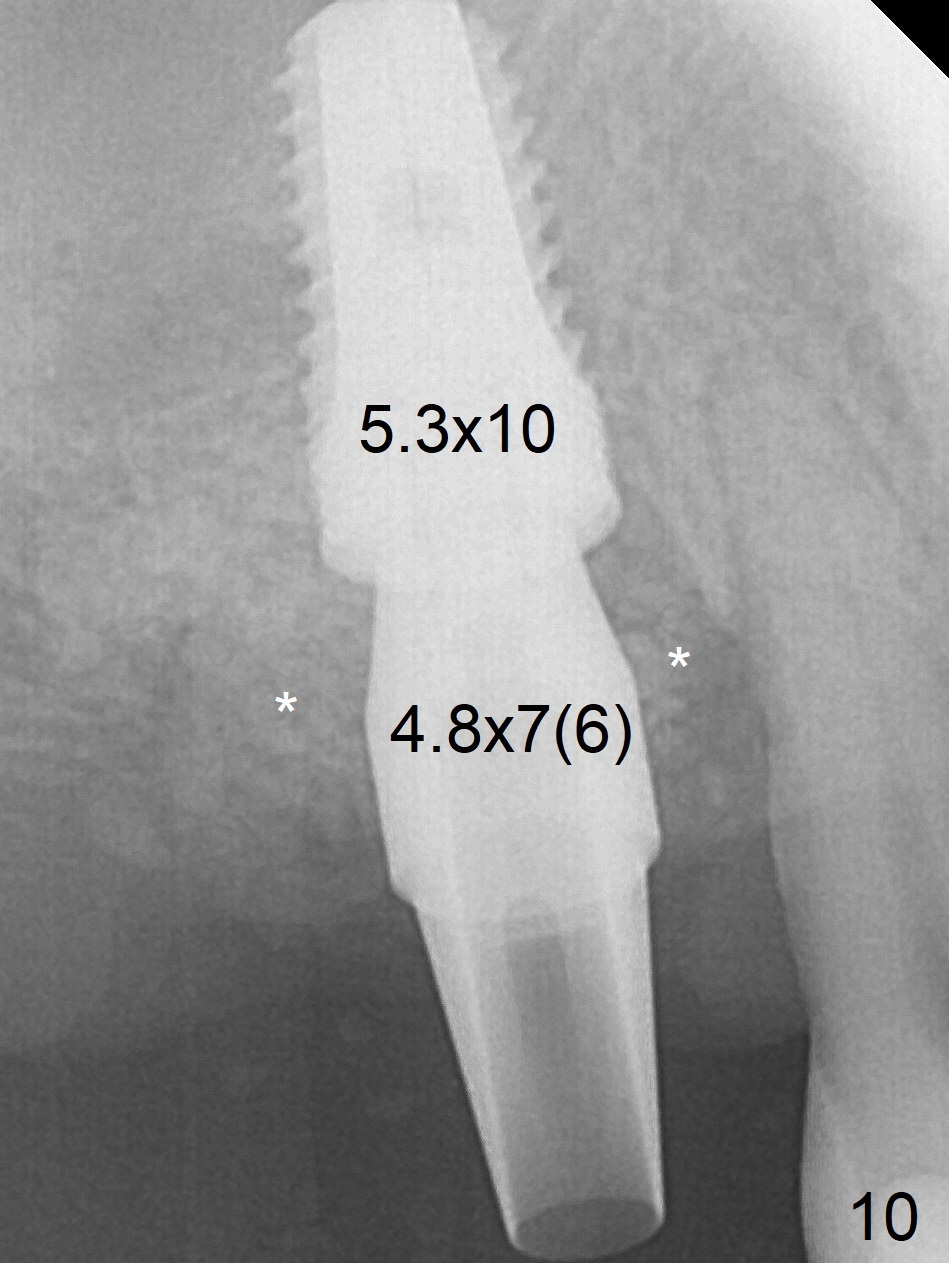

Buccal Socket Placement

After extraction of the tooth #3 (Fig.1,2), the palatal socket (P) is as wide as the buccal one (B; Fig.3,4 (socket impression)), as compared to the roots), suggesting bone loss is more severe palatally than buccally. There is a circular area in the buccal slope of the palatal socket, in which the bone looks thin (purplish: presumably the sinus membrane underneath, Fig.5,7 (blue circle)). It appears that the palatal slope of the buccal socket (Fig.6, 7 red dashed line) is the most appropriate site for osteotomy (Fig.8). Prior to inserting 5.3 mm tap drill (Fig.9), the mesiopalatal region of the osteotomy (corresponding to the blue circle in Fig.7) perforates without sinus membrane tear. A small piece of Osteogen plug is placed in the perforation before inserting a 5.3x10 mm SM implant (Fig.10,11). Following placement of another piece of Osteogen plug in the palatal socket and of a 4.8x7(6) mm abutment, mineralized cortical and cancellous bone is placed (*). Collagen plug and an immediate provisional are used to close the socket opening. CT taken 11 months post cementation shows that the implant is placed within bony boundary, although buccally (Fig.12 B). Bone graft seems to heal in the sinus (Fig.13 (sagittal section),14 (coronal section) white * (Osteogen plug) and in the socket (brown * (allograft and Osteogen)).